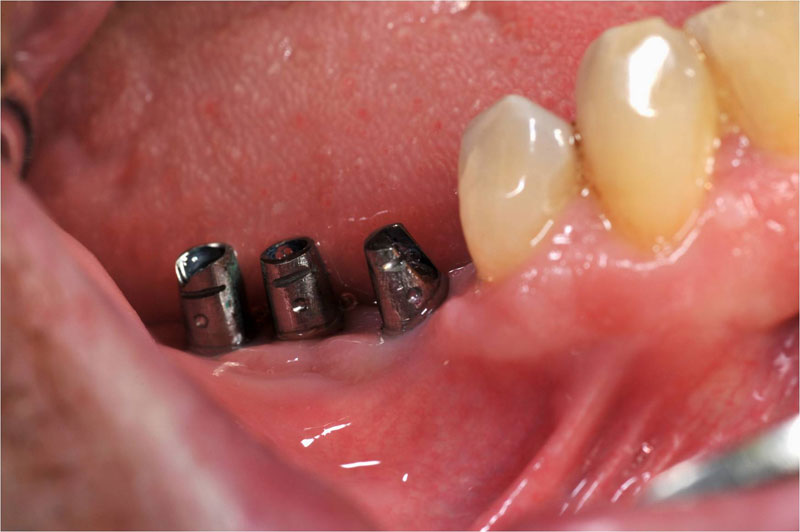

Fehlen in der Front oder im Seitenzahnbereich mehrere Zähne, ist eine Brücke oder Prothese vollkommen unnötig. Die fehlenden Zähne können entweder einzeln durch eine entsprechende Anzahl von Implantaten oder durch implantatgetragene festsitzende Brücken ersetzt werden. Das Bild der Kronen zeigt die drei Verschraubungen deutlich, im Mund liegen diese verdeckt am Gaumen oder im Bereich der Zunge.